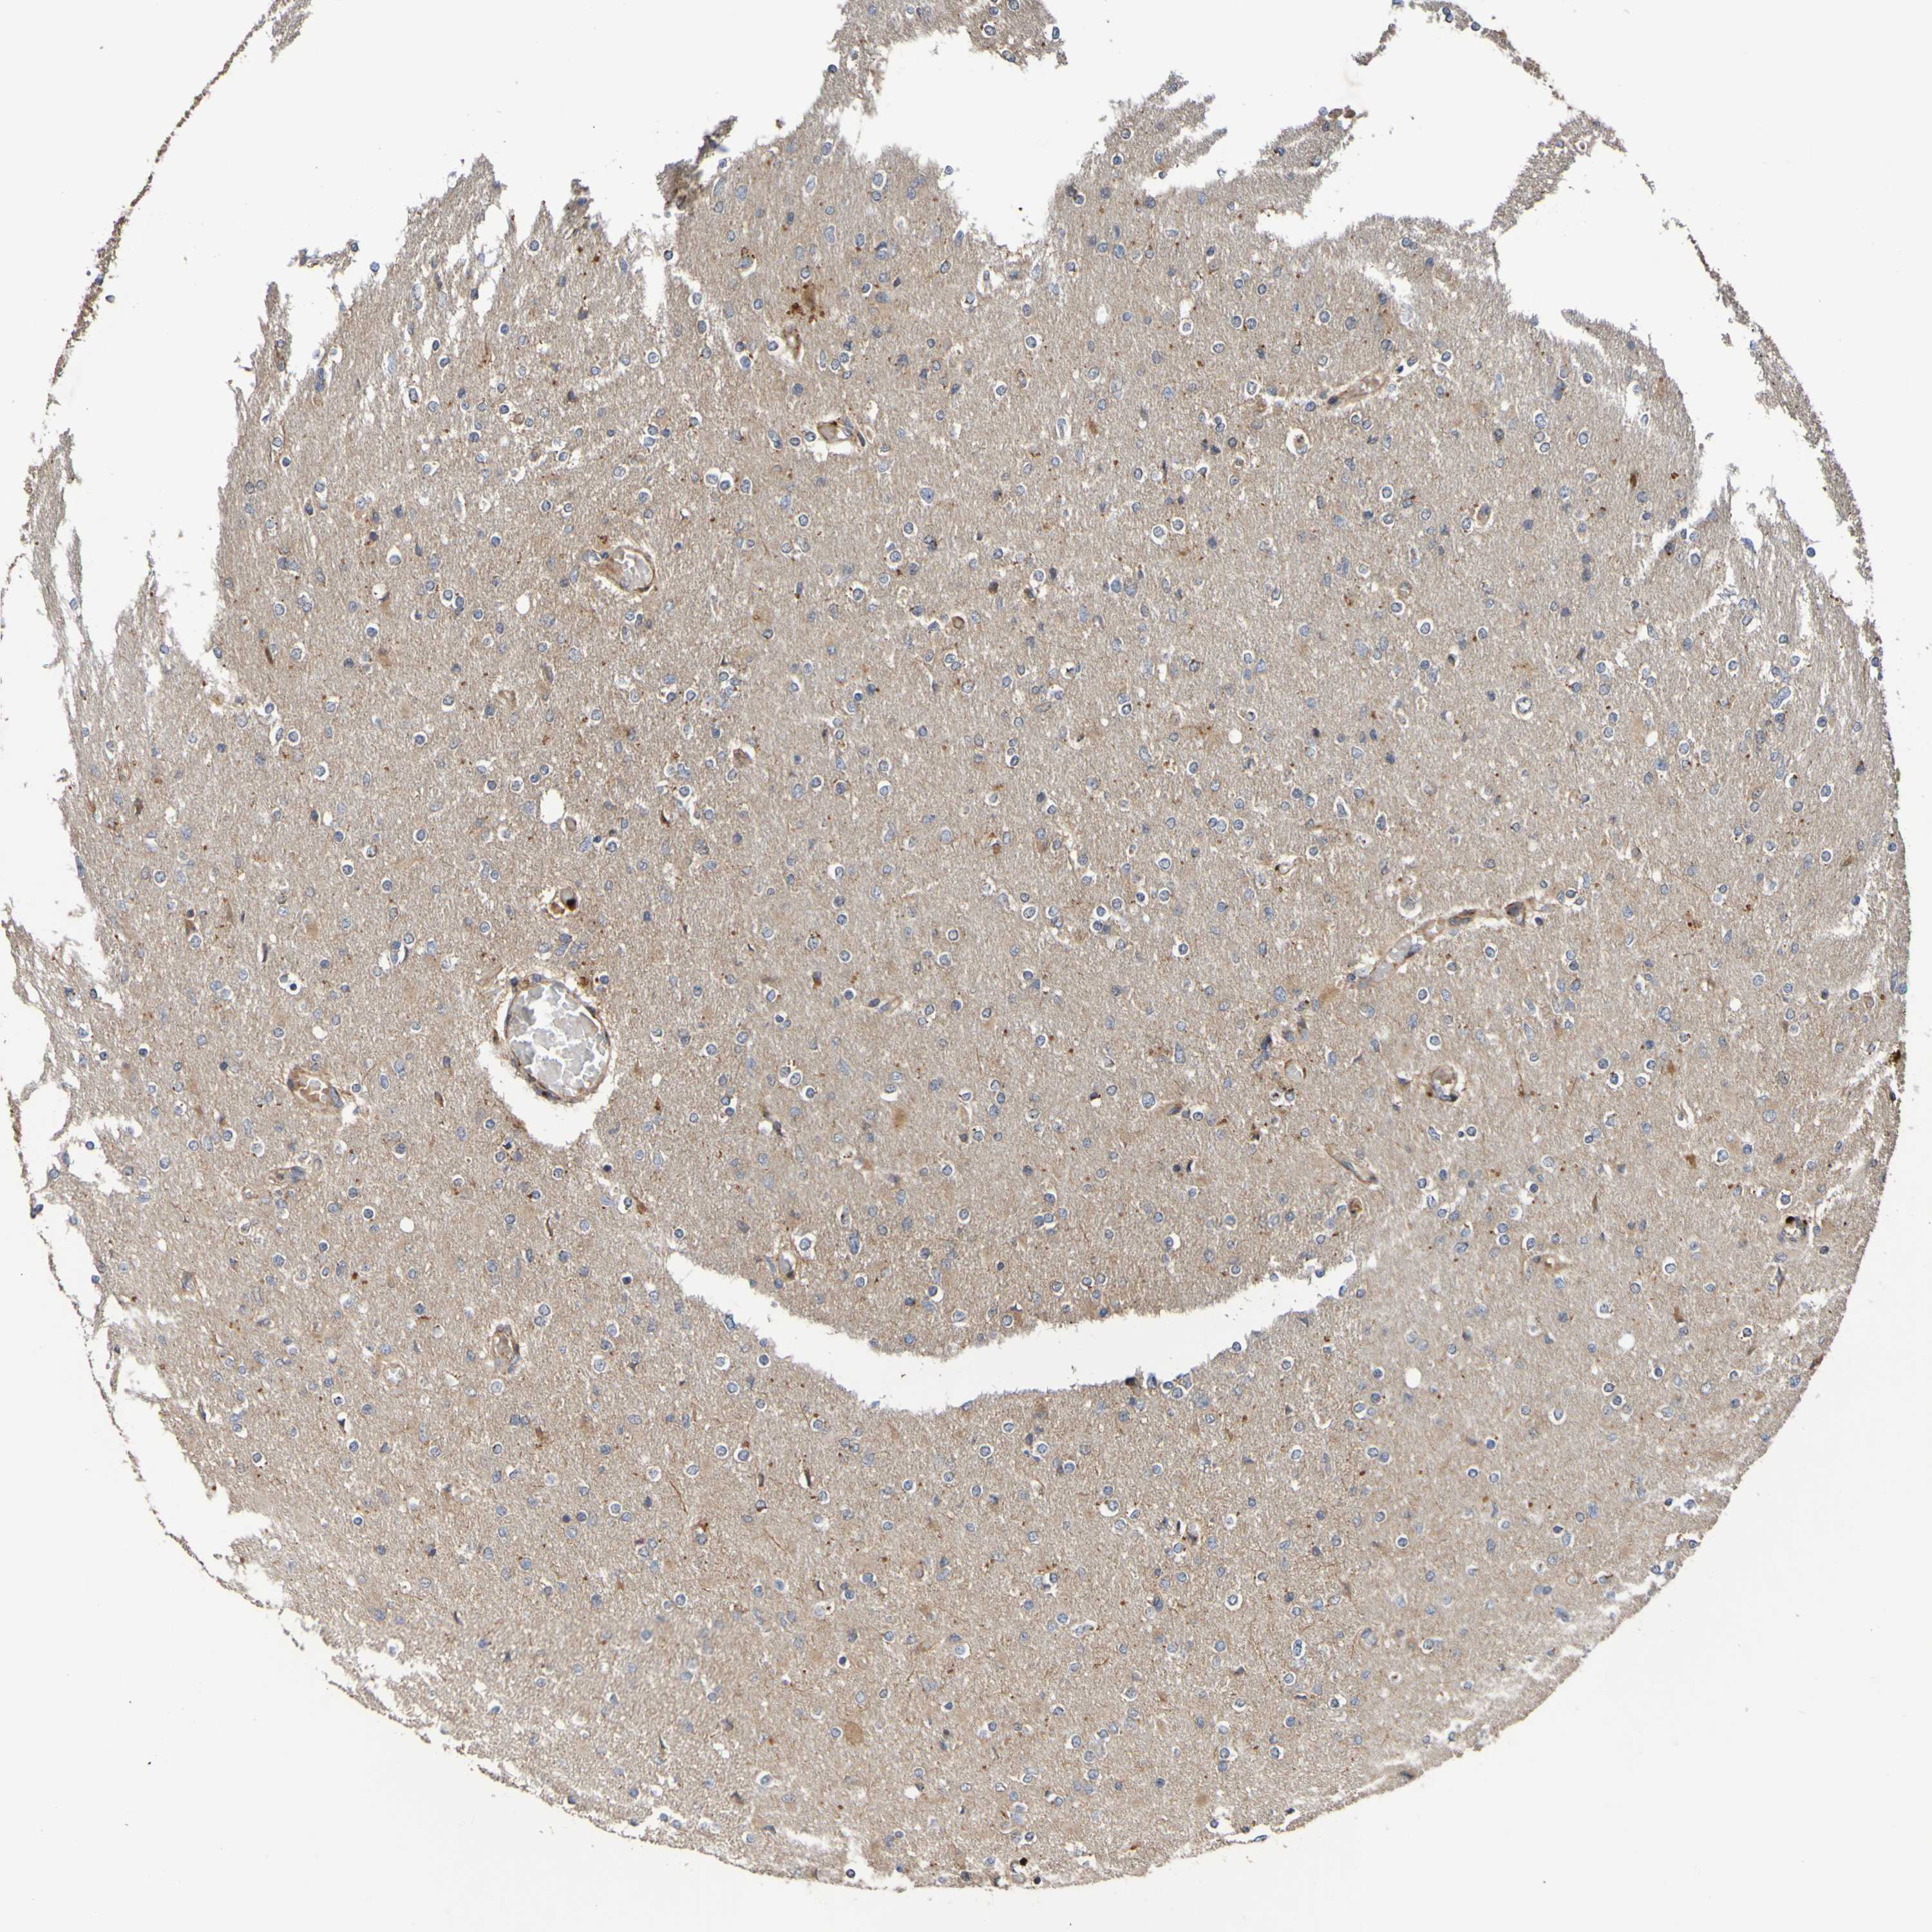

GLIOMA - Protein expressioni

A mouse-over function shows sample information and annotation data. Click on an image to view it in a full screen mode. Samples can be filtered based on level of antibody staining by selecting one or several of the following categories: high, medium, low and not detected. The assay and annotation is described here.

Note that samples used for immunohistochemistry by the Human Protein Atlas do not correspond to samples in the TCGA dataset.

Antibody stainingi

Antibody staining in the annotated cell types in the current human tissue is reported as not detected, low, medium, or high, based on conventional immunohistochemistry profiling in selected tissues. This score is based on the combination of the staining intensity and fraction of stained cells.

Each image is clickable and will lead to virtual microscopy that enables deeper exploration of all samples and also displays staining intensity scores, fraction scores and subcellular localization as well as patient and tissue information for each sample.

Antibody CAB010911

Staining

High

Medium

Low

Not detected

Intensity

Strong

Moderate

Weak

Negative

Quantity

>75%

75%-25%

<25%

None

Location

Nuclear

Cytoplasmic/membranous

Cytoplasmic/membranous,nuclear

Glioma, malignant, High grade

Glioma, malignant, Low grade